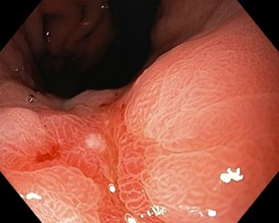

Эндоскопическая классификация стадий течения язвенного процесса по Sakita-Miwa

|

A1 |

H1

S1

A2

H2 |

S2 |

Рисунок 1. Стадии регрессии (заживления) язвы желудка и их характерные черты:

A (Active). Активная стадия (обострение)

A1. Слизистая оболочка, окружающая язву, выглядит набухшей в результате отёка, регенерация эпителия отсутствует.

A2. Отёк слизистой оболочки вокруг язвы уменьшился, край язвы отчётливо виден и в крае язвы появились первые ростки регенерирующего эпителия. По периметру язвы часто прослеживается красный ободок, а непосредственно по краю – циркулярный белый струп. Обычно, сходящиеся складки слизистой оболочки прослеживаются вплоть до края язвы.

H (Healing). Стадия заживления

H1. Слой белого фибрина, покрывающий язву, становится тонким, а регенерирующий эпителий распространяется непосредственно на основание язвы. Градиент между краем и дном язвы сглаживается. Но кратер язвы все еще очевиден, и край язвы отчётливо виден. Диаметр язвенного дефекта составляет примерно от половины до двух третей диаметра язвы в стадии A1.

H2. Язвенный дефект меньше, чем в стадии H1, и регенерирующий эпителий покрывает большую часть дна язвы. Площадь слоя белого фибрина составляет примерно от четверти до трети площади язвы в стадии А1.

S (Scarring). Стадия рубца

S1. Регенерирующий эпителий полностью покрывает дно язвы. Белый слой фибрина полностью исчез. Первоначально зона регенерации выглядит ярко красной. При прицельном осмотре можно увидеть большое количество капилляров. Сформировался "красный рубец".

S2. В срок от нескольких месяцев до нескольких лет исходно красный рубец принимает цвет окружающей слизистой оболочки. Сформировался «белый рубец».

Комментарий. Плановое эндоскопическое исследование подтверждает наличие язвенного дефекта, уточняет его локализацию, форму, размеры, глубину, состояние дна и краев язвы, позволяет выявить признаки пенетрации, рубцовой деформации и стенозирования просвета органа. Плановое эндоскопическое исследование дает возможность обнаружить другие сопутствующие изменения слизистой оболочки и определить нарушения гастродуоденальной моторики. Для оценки стадии язвенного процесса (обострение, заживление, рубцевание) целесообразно использовать общепринятую в мире классификацию Sakita-Miwa (рис.1).